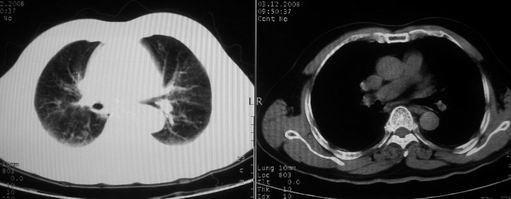

ct左肺下叶大片状高密度影,病变密度不均,界限不清,左侧胸腔积液,治疗后复查临床症状好转而影像学表现病变有发展,还是首先考虑感染性病变,复查时间短附合感染性病变的病理改变。

两肺炎症感染(以左肺下叶为著),双侧少量胸腔积液;建议继续抗炎治疗。